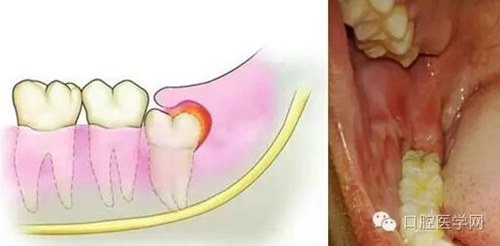

牙齒萌出困難稱為"阻生齒"或"埋伏牙"。阻生齒最常見(jiàn)于下頜第三磨牙,此牙萌出年齡在20歲左右,故稱為"阻生智齒"。阻生智齒會(huì)產(chǎn)生下列危害:

(1)冠周炎:智齒因阻生而使牙冠不能完全外露,牙冠周圍的牙齦成袋狀,極易積存食物、滋養(yǎng)細(xì)菌。當(dāng)全身抵抗力下降時(shí)引起急性冠周炎。

2.jpg